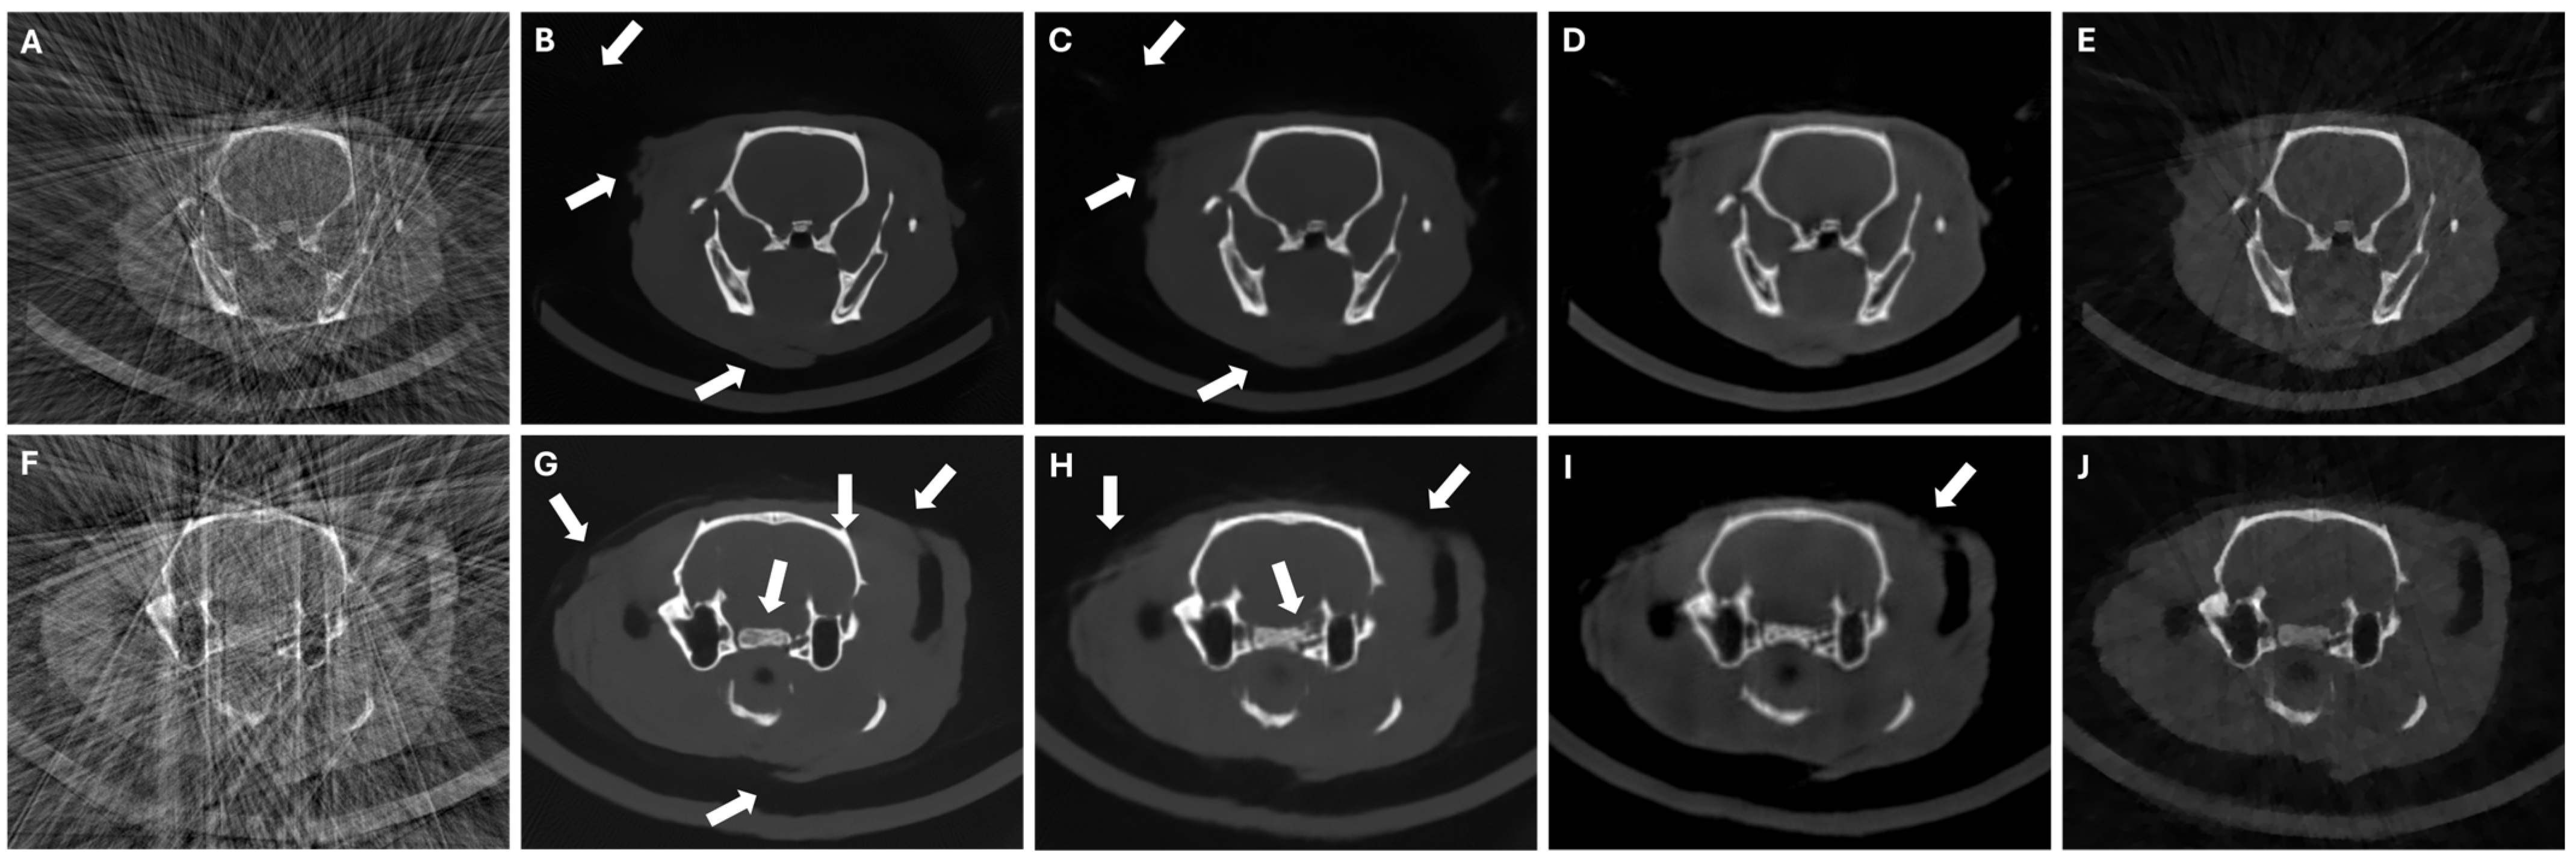

Figure 7 shows that DeepBH, SART-PICCS, and PICDL were able to correct the deformations caused by the reduced span angle (see white arrows in Figure 7A and Figure 7F), leading to PSNR and SSIM improvements with PICDL as high as 100% and 67%, respectively (Table 4). While SART-PICCS introduced blurring in the reconstructed image owing to the downsampled prior, PICDL could recover high-resolution edges.

Figure 7.

Central axial slices of FDK reconstructions (A,F), DeepBH reconstructions (B,G), prior images (C,H), SART-PICCS reconstructions (D,I), and PICDL reconstructions (E,J) for the two test animals in LSA scenario of 120 and 130 projections, respectively. Arrows indicate the LSA artifacts.

In the case of the LNP scenario, while we see an elimination of beam-hardening artifacts and streaks with all methods, DeepBH showed some hallucinations in the form of new or incomplete structures (see white arrows Figure 8B and Figure 8G). While SART-PICCS transferred the hallucinations of the prior image into the reconstructed image, PICDL was able to avoid them (Figure 8E and Figure 8J), resulting in an increased PSNR and SSIM of more than 86% and 121%, respectively, compared to FDK.

Figure 8.

Central axial slices of FDK reconstructions (A,F), DeepBH reconstructions (B,G), prior images (C,H), SART-PICCS reconstructions (D,I), and PICDL reconstructions (E,J) for the two test animals in LNP scenario of 49 and 42 projections, respectively. Arrows indicate hallucinations.